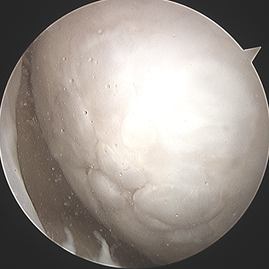

수술 전후 사례

수술 후 1년

수술 전

카티스템 줄기세포 연골재생술(Cartistem)

제대혈 유래 줄기세포 치료제(카티스템)은 큰 연골손상이나 퇴행성 관절에서도 적용 가능하며, 더 질 좋은 연골 재생을 기대하는 수술입니다.

3줄기세포 제제(카티스템)를 병변 부위에 채워 넣고 고정 한다.

4봉합후 마무리 한다. 줄기세포가 더 질이 좋은 연골(유리연골 유사 조직)을 형성하도록 도와준다.